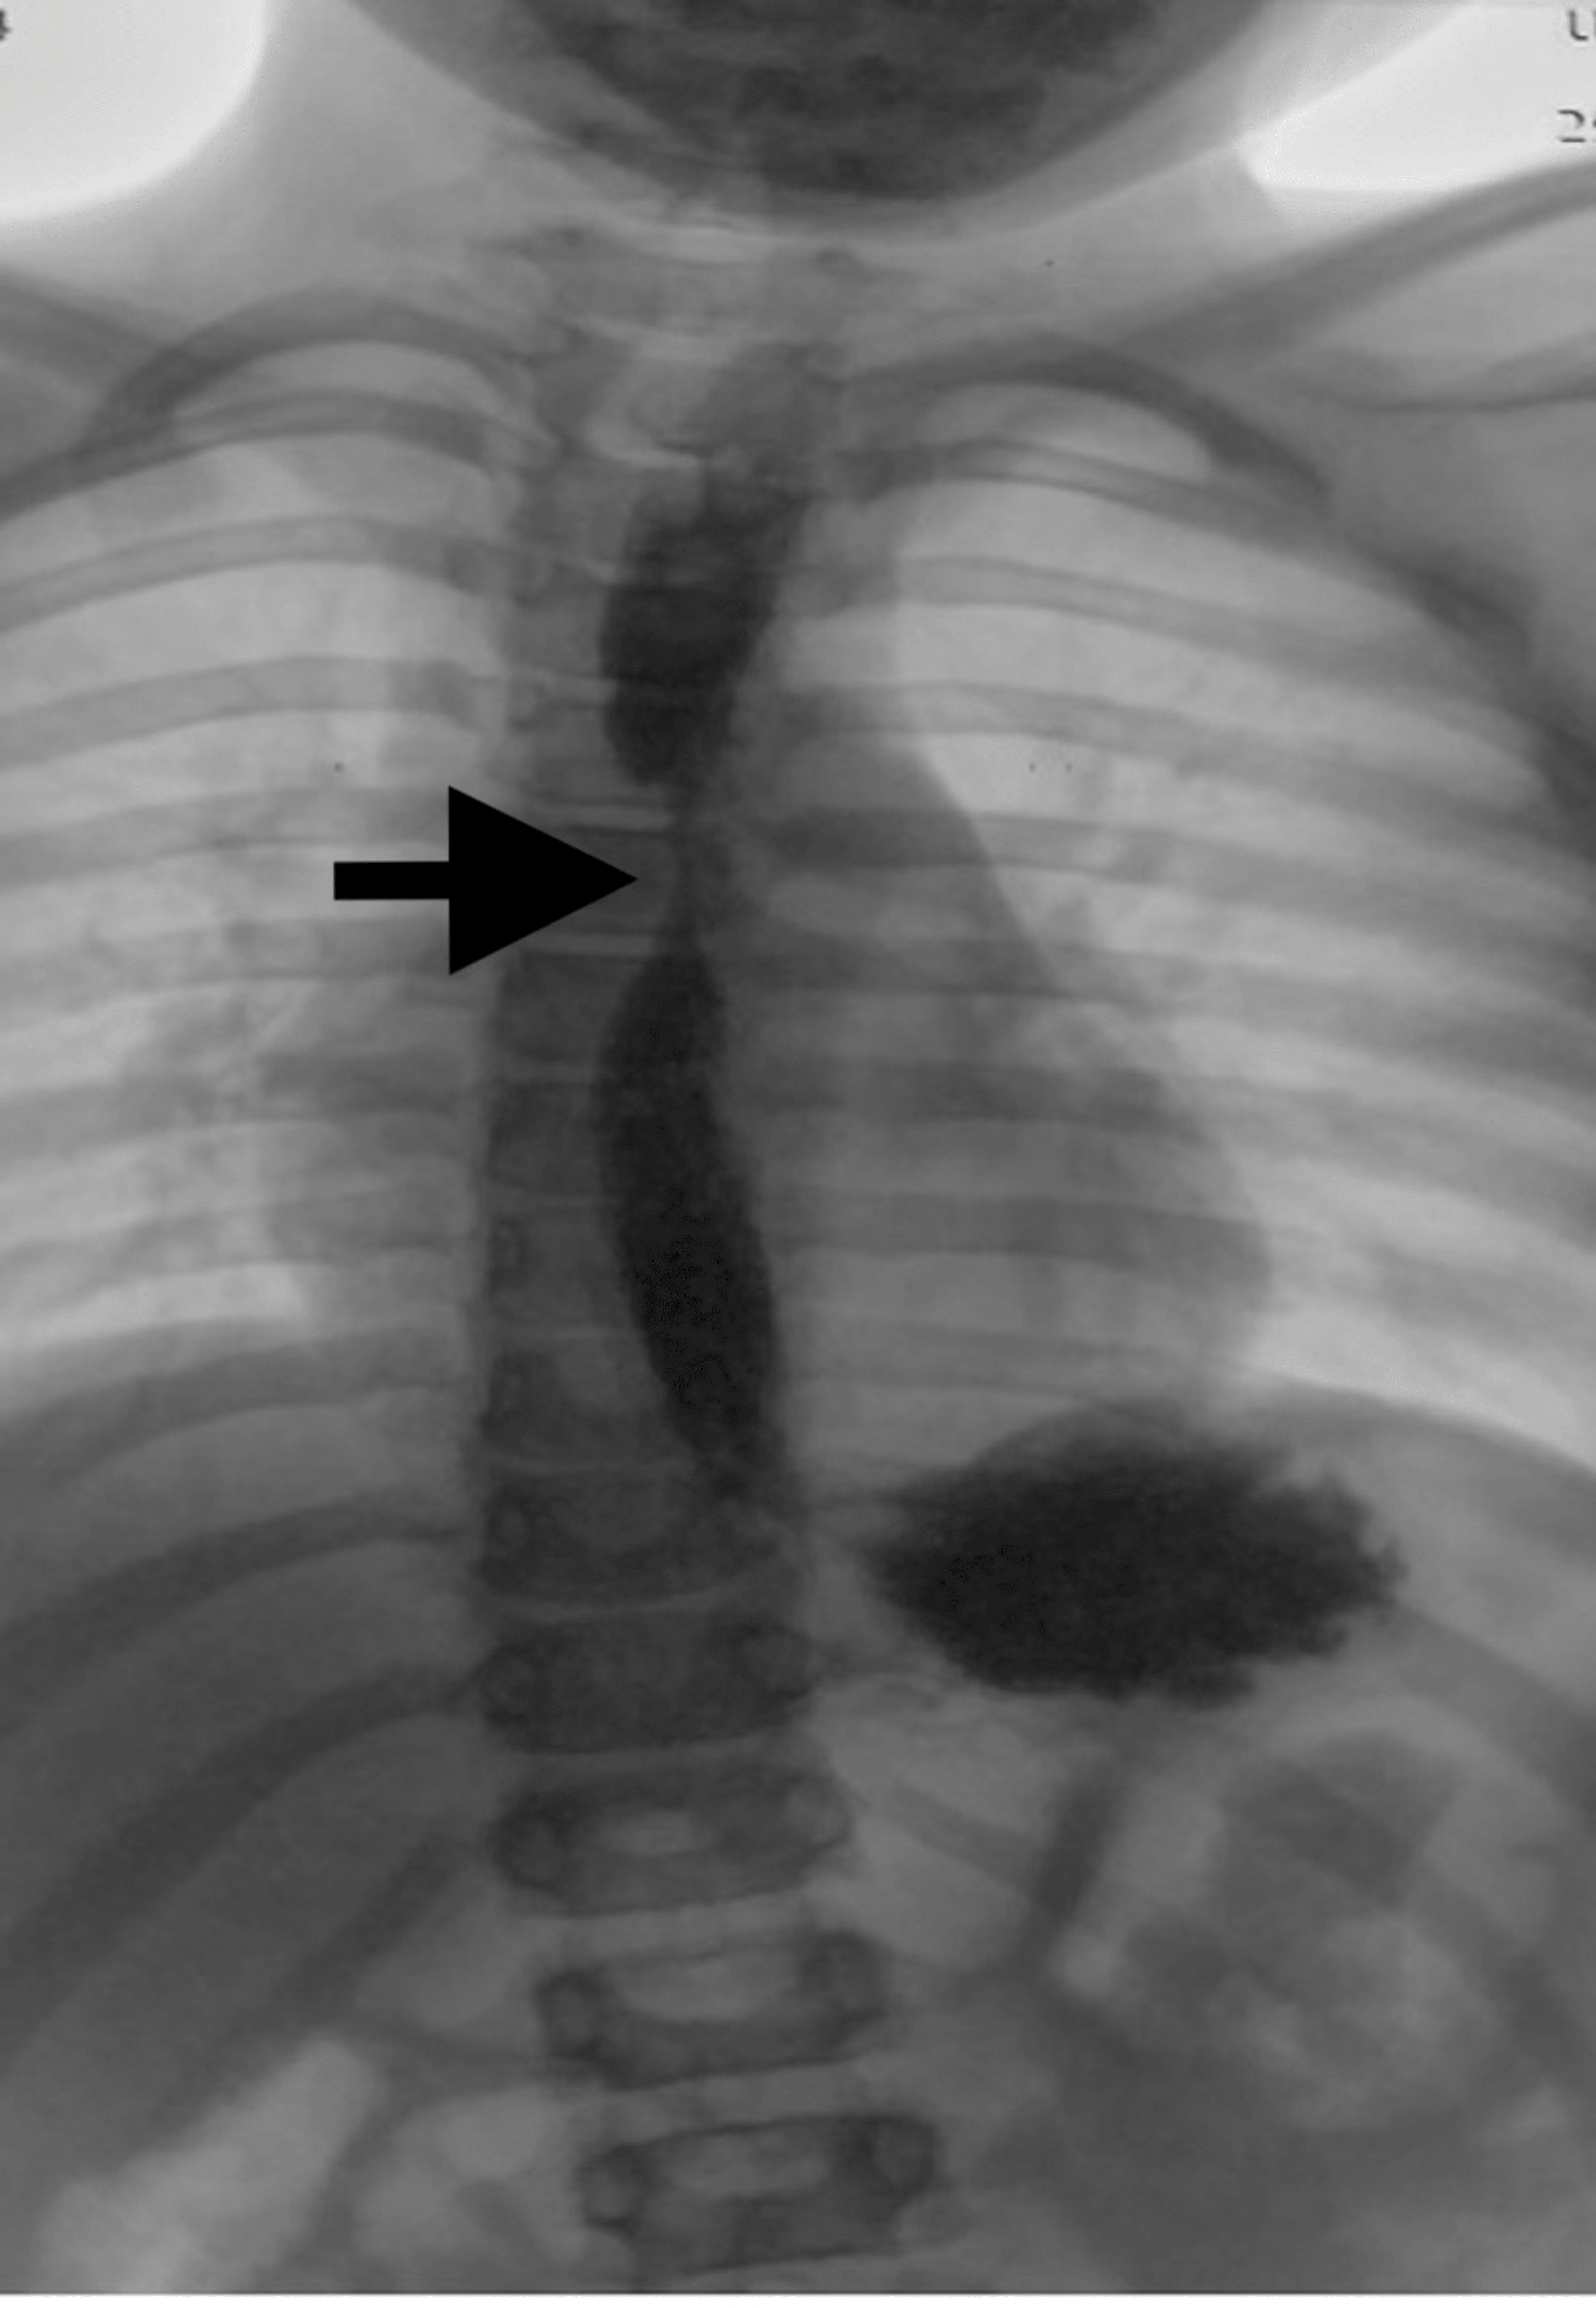

Radiographyesophageal post caustic stenosis. Download Scientific Diagram Caustic Esophagitis — meanwhile, gastrointestinal stricture is the most common late sequela of caustic ingestion, with the esophagus being. — esophageal motility studies report low amplitude and nonperistaltic. — caustic ingestions are seen most often in young children between one and three years of age and can cause. — caustic substances injure tissue by means of a chemical. Caustic Esophagitis.

Contrast esophagogram shows severe esophageal stenoses secondary to Caustic Esophagitis — the degree of esophageal injury at endoscopy is a predictor of systemic complication and death with a 9. — caustic ingestions are seen most often in young children between one and three years of age and can cause. — esophageal motility studies report low amplitude and nonperistaltic. Caustics (strong acids and alkalis), when ingested, burn upper. Caustic Esophagitis.

A contrast study of the esophagus showing severe caustic stricture Caustic Esophagitis — caustic substances injure tissue by means of a chemical reaction on direct physical contact. — esophageal motility studies report low amplitude and nonperistaltic. — the degree of esophageal injury at endoscopy is a predictor of systemic complication and death with a 9. — caustic ingestion can cause severe injury to the esophagus and the stomach.. Caustic Esophagitis.

Caustic stricture of the middle third of the esophagus with upstream Caustic Esophagitis — the degree of esophageal injury at endoscopy is a predictor of systemic complication and death with a 9. — meanwhile, gastrointestinal stricture is the most common late sequela of caustic ingestion, with the esophagus being. — caustic ingestion can cause severe injury to the esophagus and the stomach. — caustic substances injure tissue by means. Caustic Esophagitis.